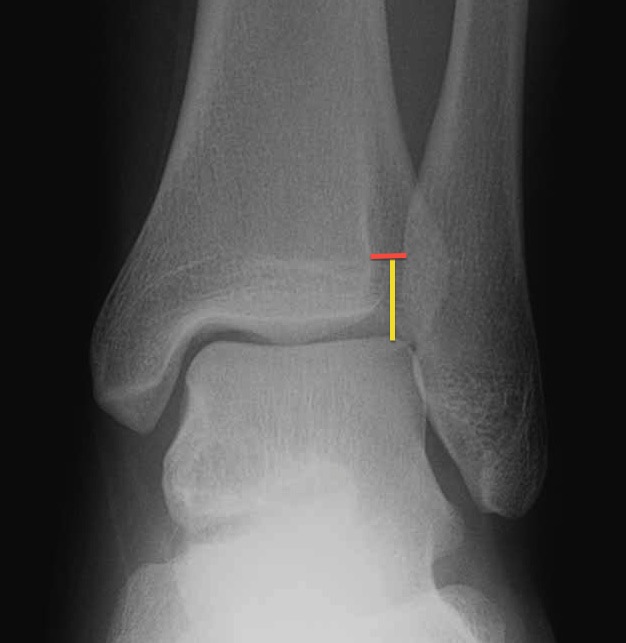

using the AP view, measure 1 cm above the tibial plafond (yellow line). lateral clear space is distance btwn lateral border of posterior tibia and medial border of fibula (red line)

if > 5 mm then syndesmosis ( RID6088 ) injury

how to draw the lateral clear space